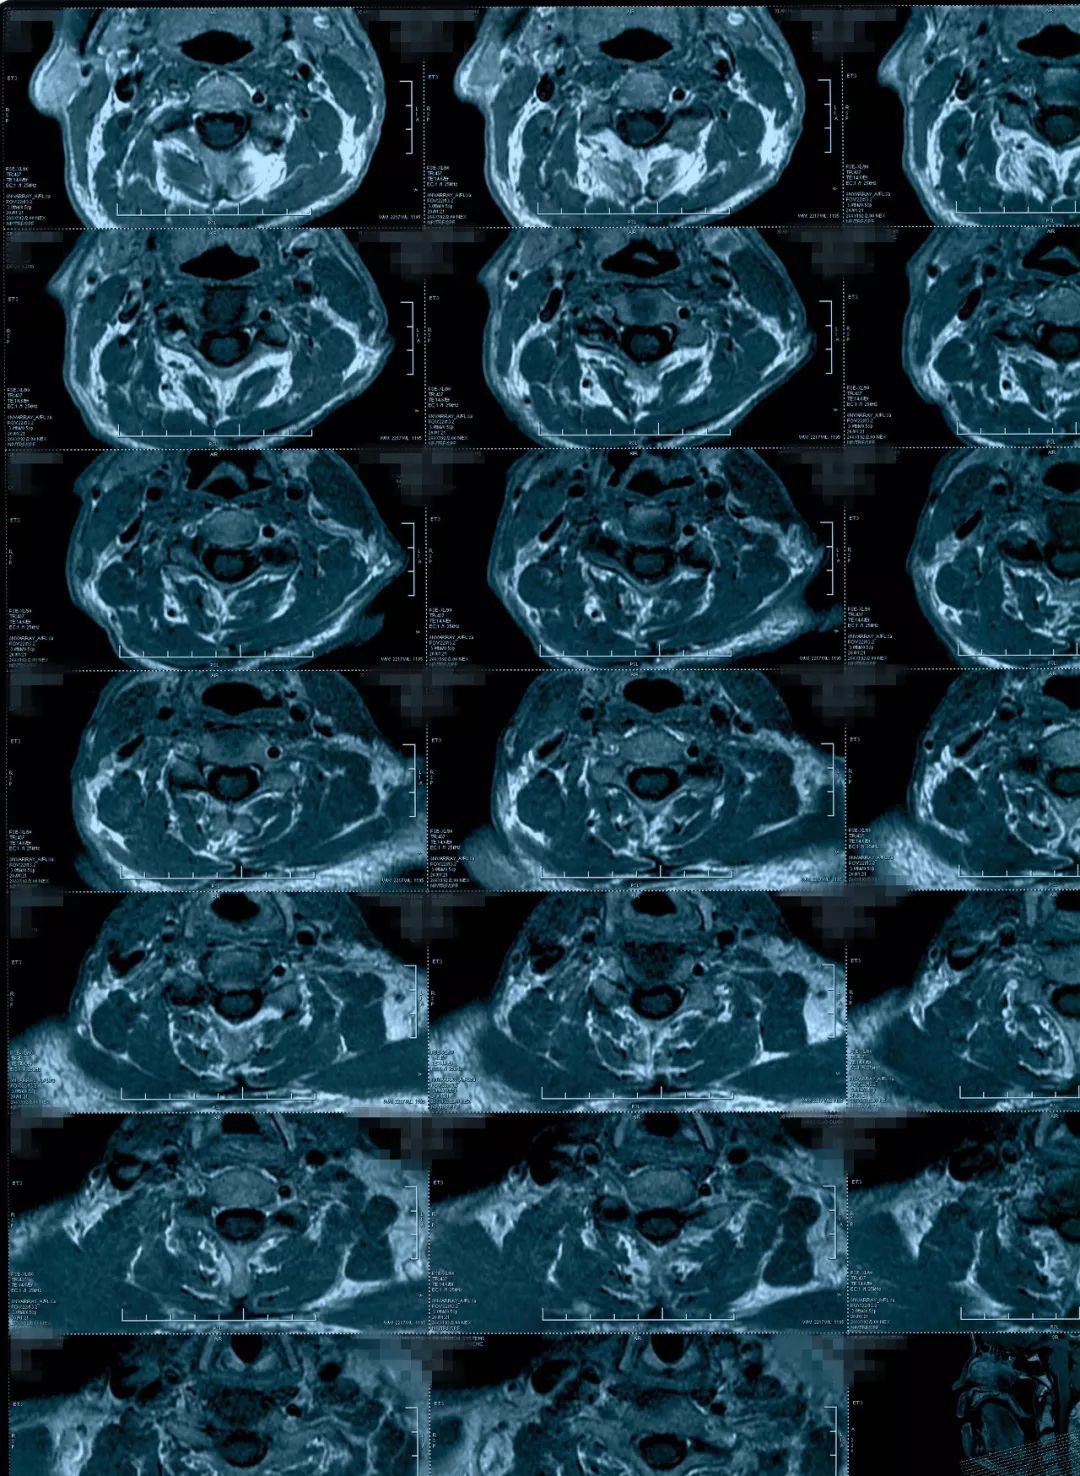

治疗后影像学资料

病人恢复得挺好,他的椎管是有一些容积减小,更主要是脊髓水肿造成的相对容积减小,如果对这种病人做椎管开大,也是能改善症状,但是毕竟病人做了一个手术,明确炎症之后做保守治疗能够恢复是更好的。明确了病因,病人本人是非常满意的,知道了自己是什么问题,最后得到了很好的治疗。